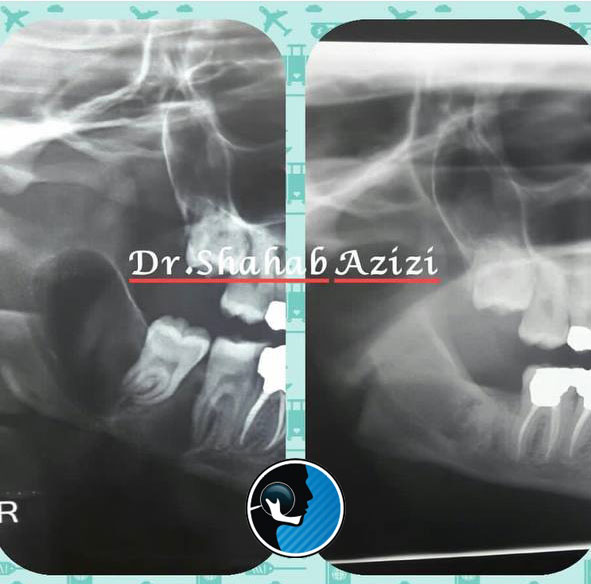

سرطان فک

سرطان فک، سرطانی است که از سایر نواحی مانند دهان یا حفره دهان به فک انتشار پیدا میکند و در برخی موارد نادر ممکن است از خود فک ناشی شود. متخصصان به طور کلی سرطان فک را نوعی نادر از…